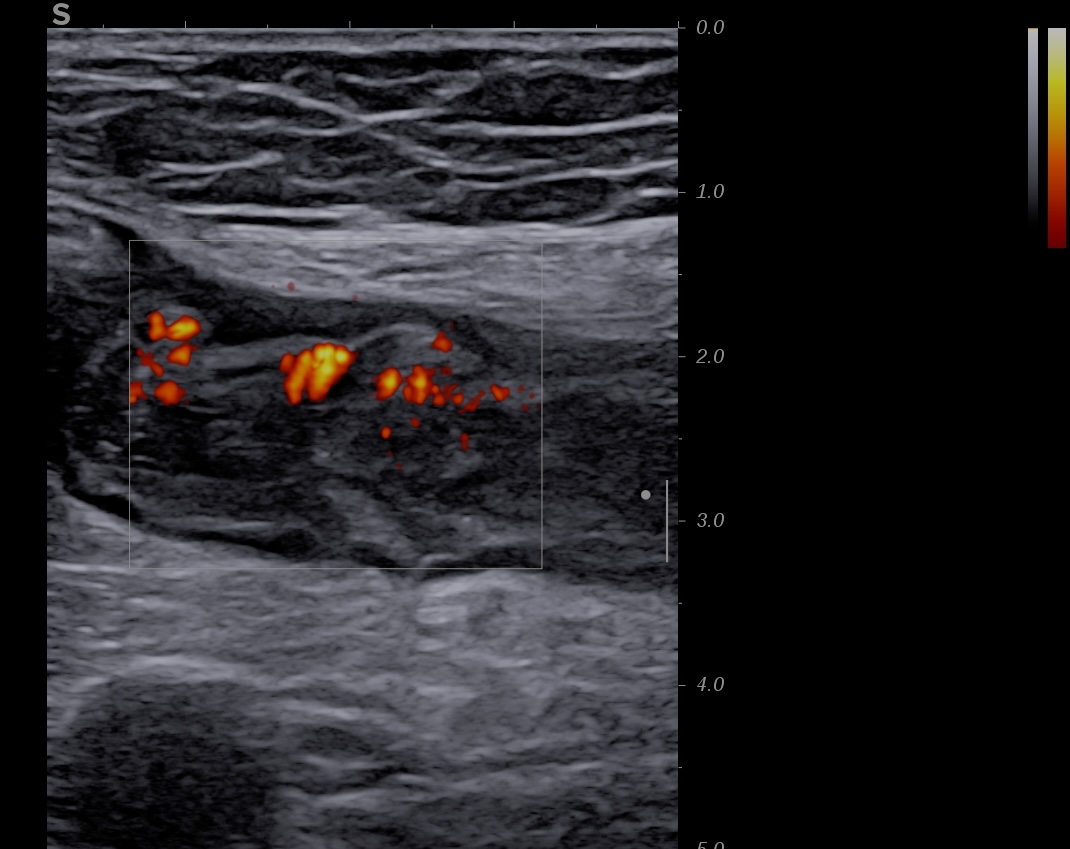

Activité Doppler limitée à la paroi, intense

- spots longs et multiples (limités à la paroi)